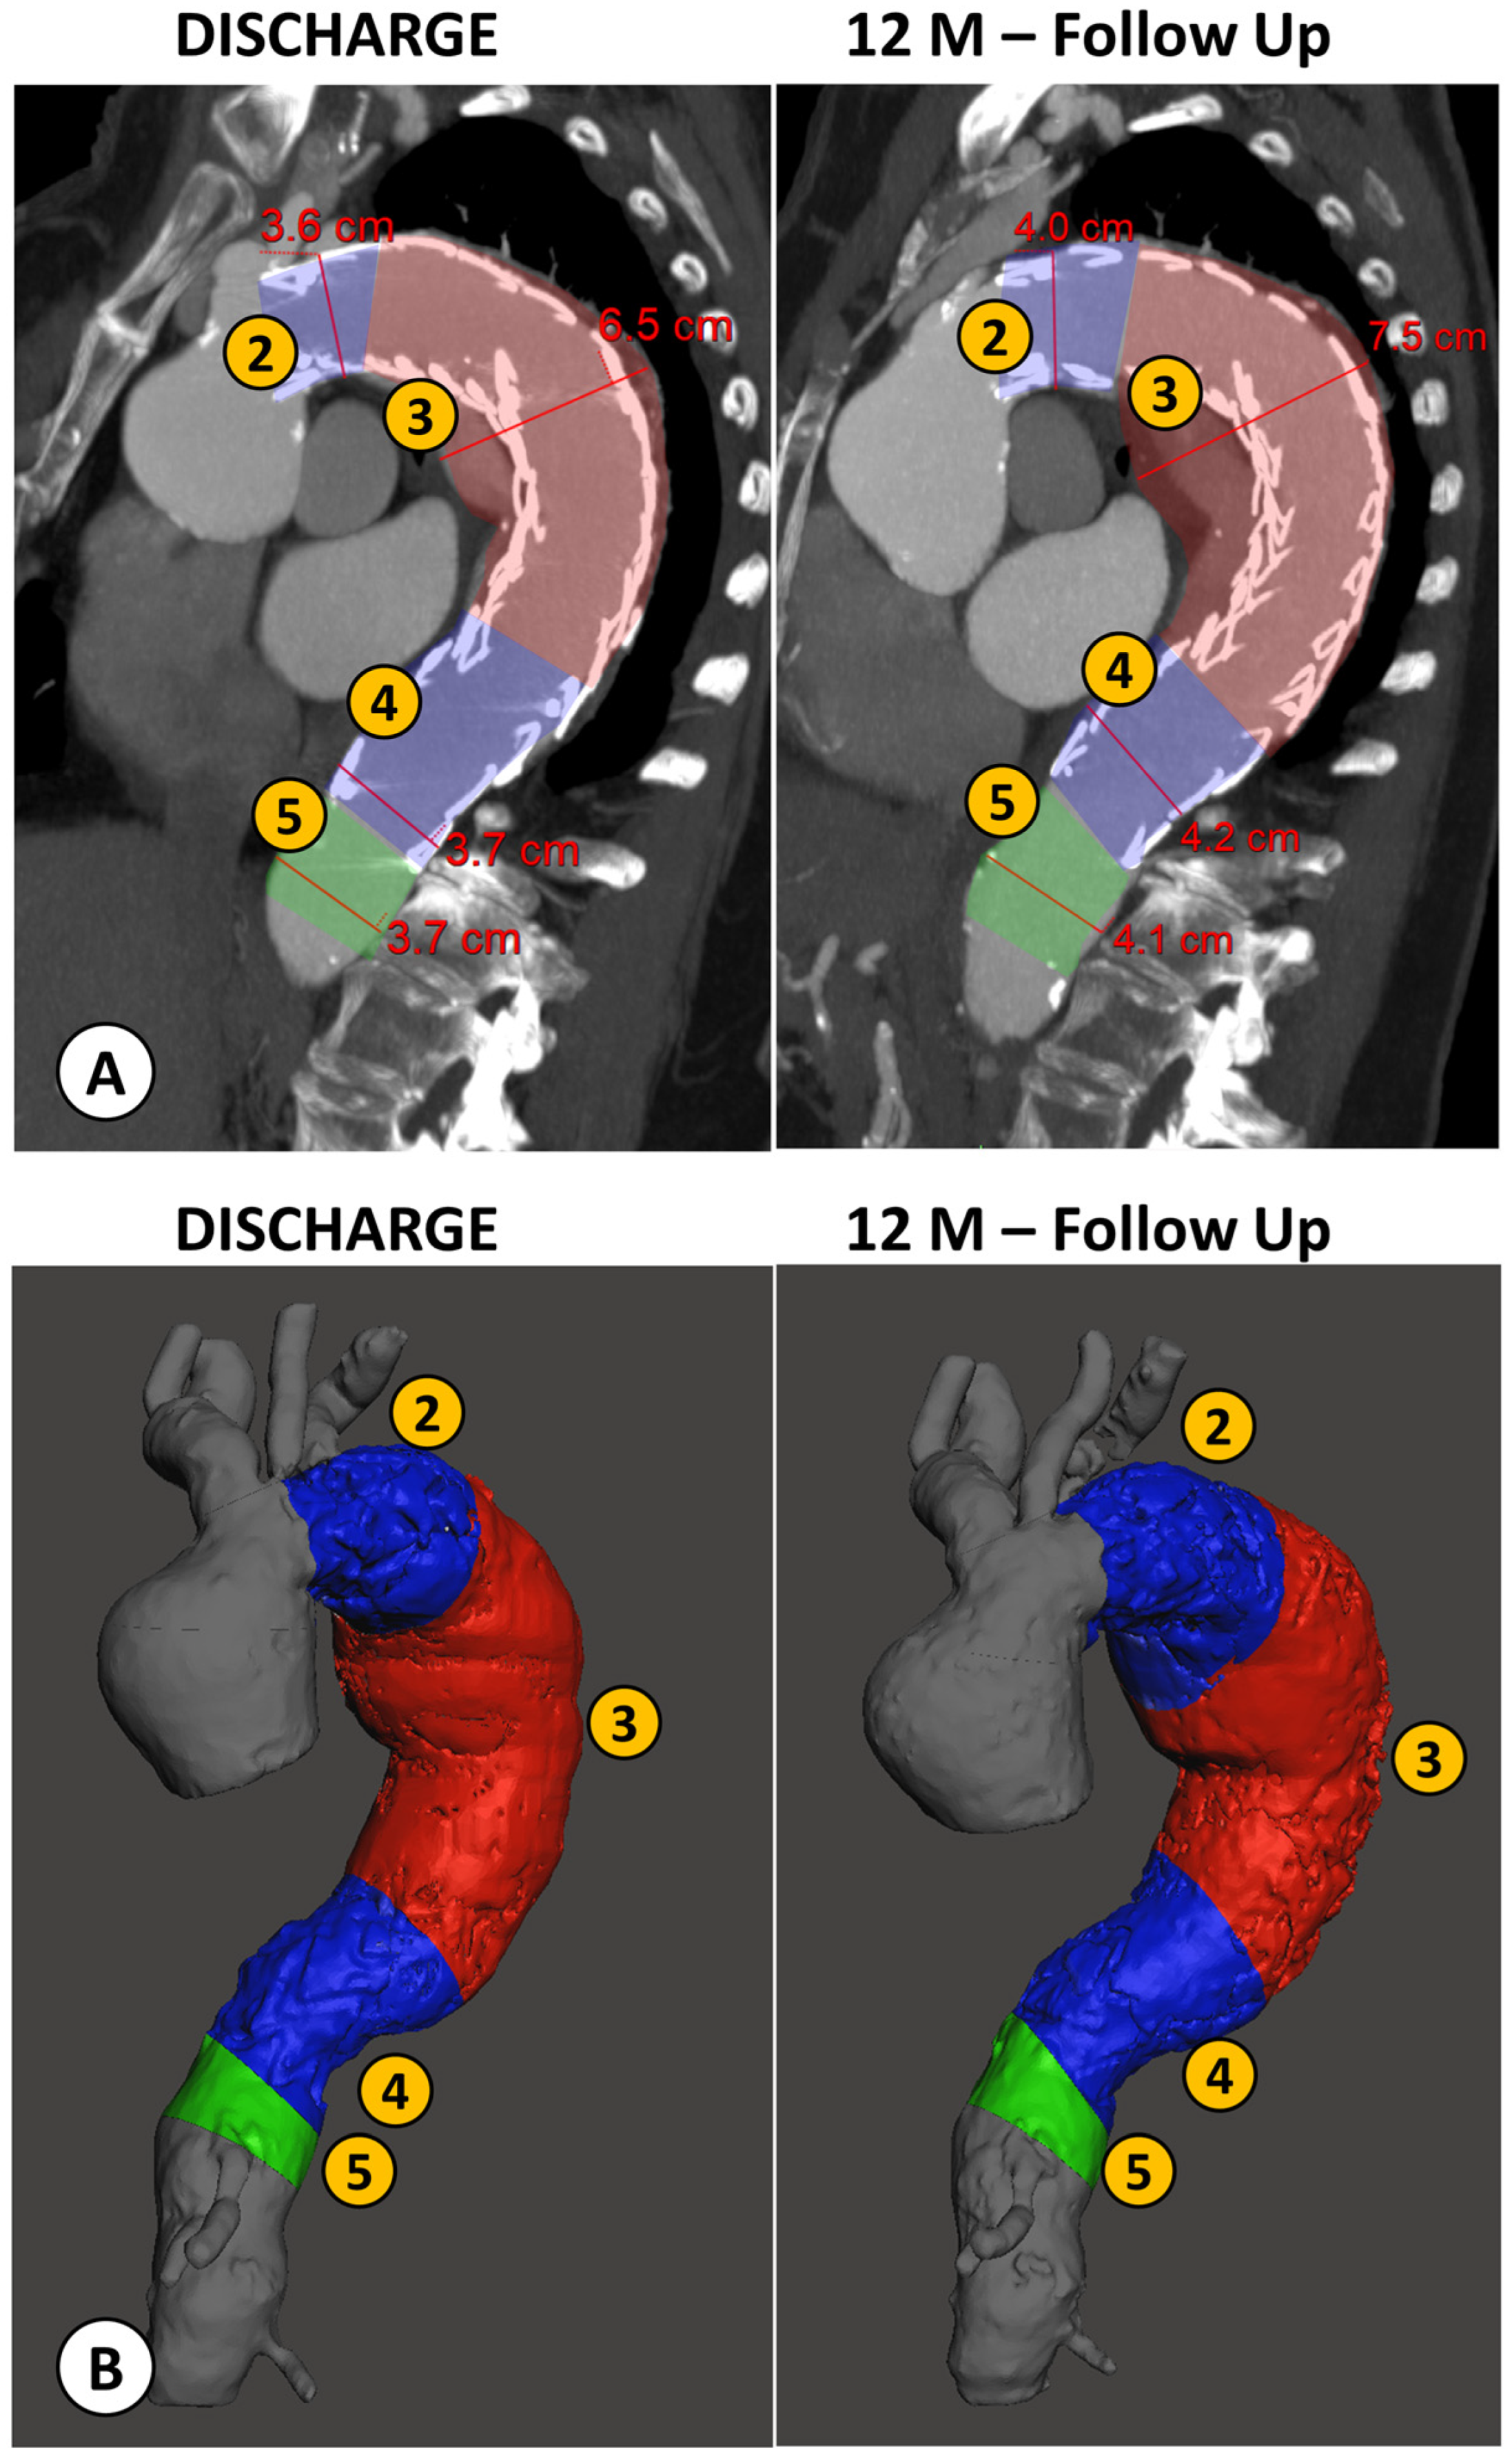

2.3. Volumetric Analysis

2.3.1. Image Segmentation

2.3.2. Volume Computation

| TEVAR-Related Complications (n = 8) | No TEVAR-Related Complications (n = 16) | Complications vs. No Complications | ||||

|---|---|---|---|---|---|---|

| Diameter Change | Net (mm) | Relative (%) | Net (mm) | Relative (%) | Net (p) | Relative (p) |

| Proximal Neck (1) | 2.5 ± 3.5 | 5.7 ± 8.0 | 1.0 ± 1.7 | 2.8 ± 5.0 | n.s. | n.s. |

| Proximal Landing Zone (2) | 0.1 ± 2.9 | 0.1 ± 7.6 | 1.1 ± 1.7 | 3.1 ± 4.5 | n.s. | n.s. |

| Aneurysm (3) | 1.5 ± 6.5 | 2.6 ± 9.5 | −2.3 ± 9.0 | −2.4 ± 12.4 | n.s. | n.s. |

| Distal Landing Zone (4) | 4.3 ± 8.4 | 10.4 ± 18.6 | 0.2 ± 3.2 | 0.9 ± 8.6 | 0.049 | 0.048 |

| Distal Neck (5) | 3.4 ± 11.3 | 8.9 ± 25.3 | 0.5 ± 2.4 | 2.1 ± 6.7 | n.s. | n.s. |

| Volume Change | Net (mL) | Relative (%) | Net (mL) | Relative (%) | Net (p) | Relative (p) |

| Proximal Neck (1) | 6 ± 1 | 26 ± 31 | 2 ± 1 | 8 ± 4 | 0.001 | n.s. |

| Proximal Landing Zone (2) | 18 ± 23 | 24 ± 22 | 4 ± 4 | 14 ± 11 | n.s. | n.s. |

| Aneurysm (3) | 13 ± 33 | 5 ± 16 | −21 ± 48 | −4 ± 24 | 0.043 | n.s. |

| Distal Landing Zone (4) | 17 ± 15 | 42 ± 51 | 3 ± 12 | 17 ± 21 | 0.022 | n.s. |

| Distal Neck (5) | 22 ± 23 | 72 ± 110 | 2 ± 8 | 5 ± 16 | 0.030 | n.s. |

| Descending Thoracic Aorta (1, 2, 3, 4, 5) | 55 ± 25 | 10 ± 5 | −11 ± 51 | 1 ± 16 | 0.001 | 0.030 |